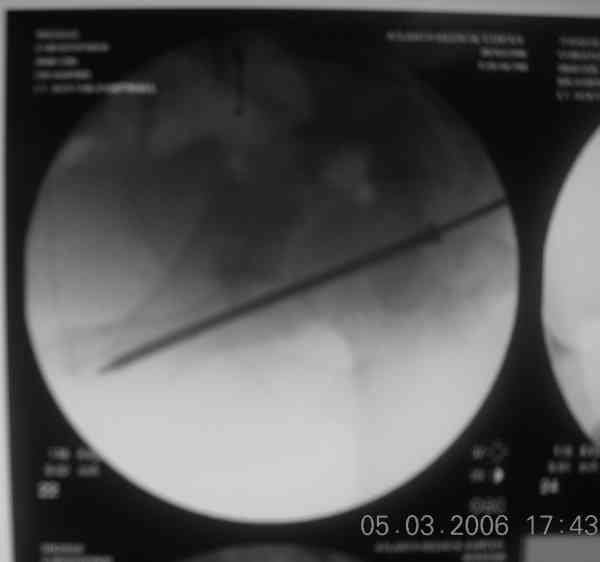

the case that I found is a 20yo male, MCC. his AP pelvis shows an interesting position of his bladder. it is pushed aside by a hematoma from SGA injury. we did a limited lateral window approach for the anterior column first, pt bumped up/supine. then closed and repositioned for KL. I could not find intra-op photos of cases when we did only a small incision for the AC screw (but they do exist!!). the lateral window is available for reduction assessment if a KL approach is being used. in the lateral position this window is available. the prone position definitely takes pressure off of the post column and facilitates reduction. in the lateral position a schantz pin in the ischial tub +/- bone hook in sciatic notch helps with PC reduction. the lateral position also gives better airway access for anesthesia. airway problems are rare, but prone position seems to be a bit more of a challenge to exchange the tube, or reintubate altogether. just something further to debate!